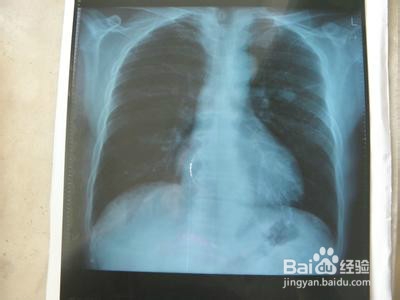

1、早起别吃饭,先去医院检查一下,拍个片子,化验一下血,确诊没啥大病,只是支气管有炎症,这下就放心了。